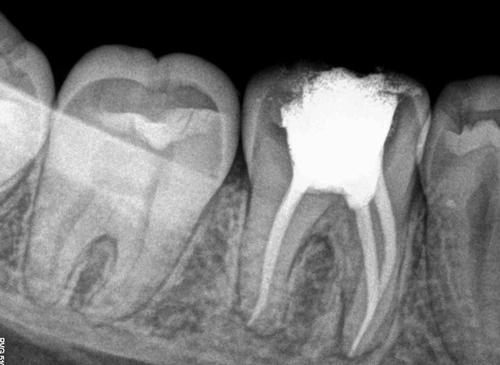

Röntgen kanal tedavisinde gerekli midir?

Teknolojinin büyük bir hızla ilerlemesinden diş hekimliği de oldukça fazla alanda faydalanmaktadır. Diş hekimliğinde kullanılan radyoloji cihazlarının teknolojisine göre hastaların aldıkları x ışını dozu da giderek azalmaktadır. Dijital görüntüleme sistemleri sayesinde görüntü anında ekrana düştüğü için tedaviler daha kısa sürelerde bitirilebilmektedir. Kök boyunu hesaplayabilmek için klasik yöntem olan röntgen çekerek kanal boyu ölçme işlemi de artık kök ucu bulucu cihazlarla (apex locator) yapıldığı için daha az röntgen çekerek tedaviler tamamlanabilmektedir.